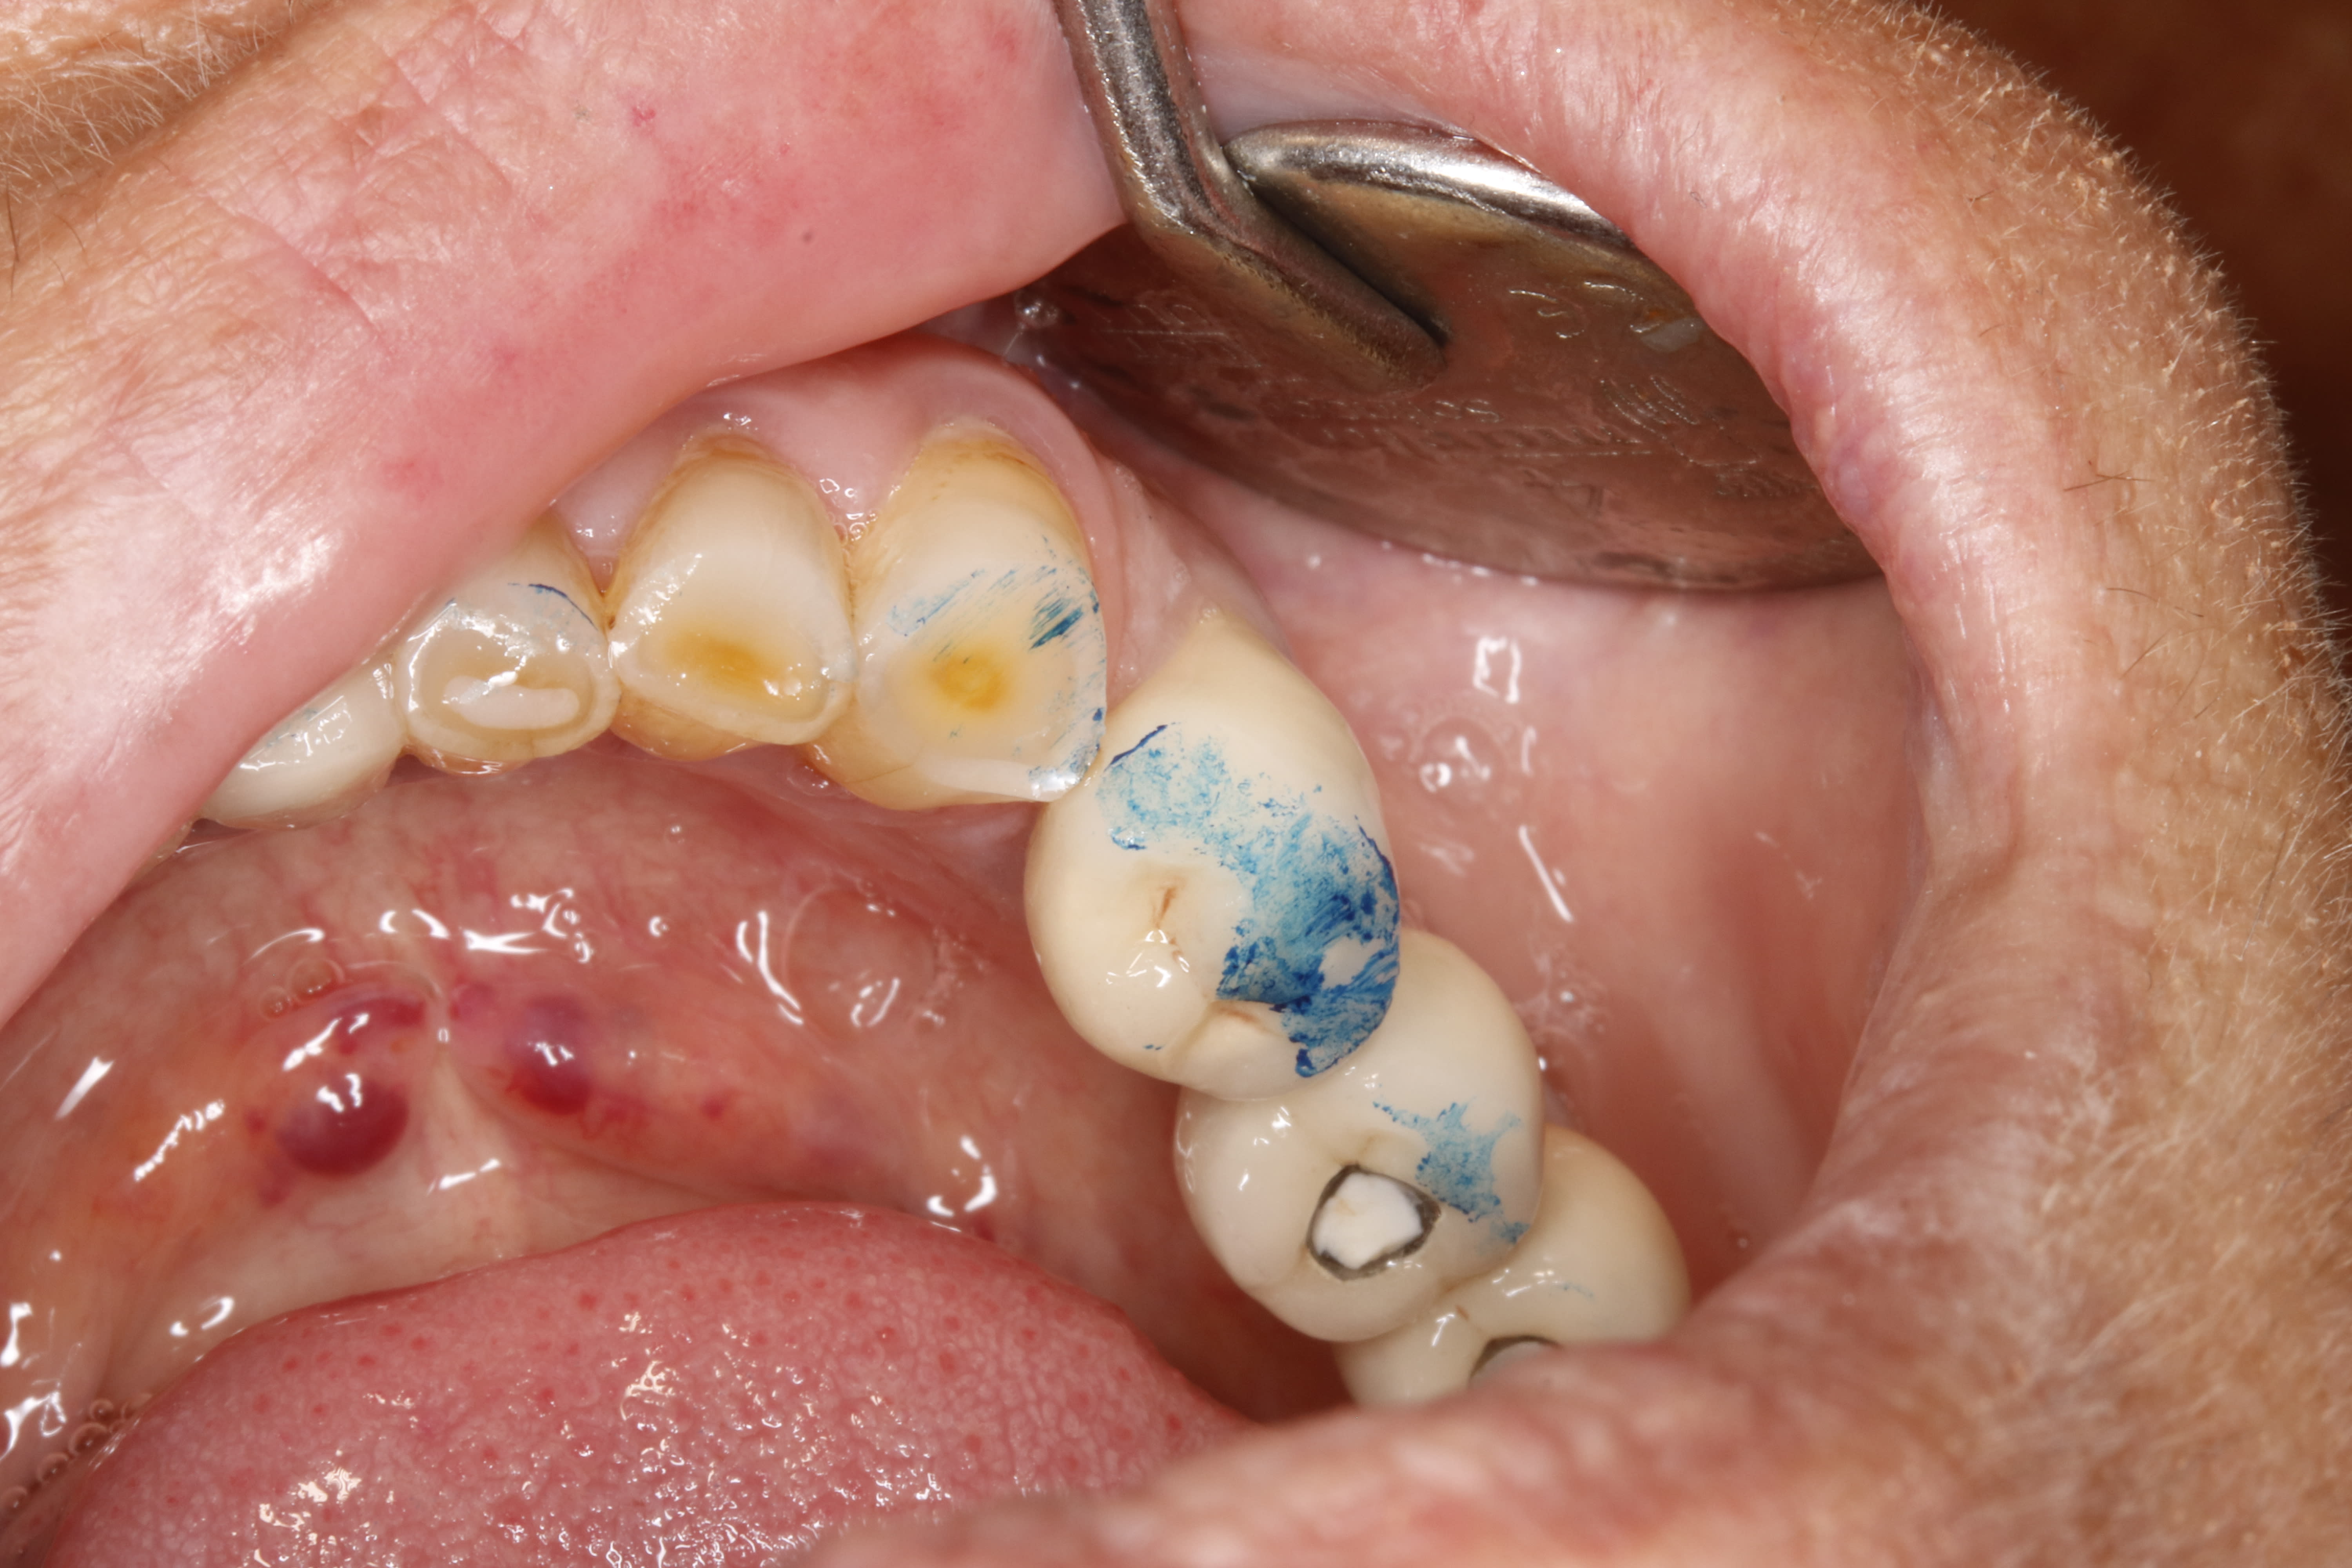

43 puis 41, mais t'as pas dit à quel mouvement correspond ton papier bleu, et t'as pas dit si le guidage gauche est enfin libéré depuis qu'elle a éclatée la pointe canine.....et au final ça ne fera pas 3000, car le devis va faire des petits, y'a tout le bas à revoir d'abord

" mais t'as pas dit à quel mouvement correspond ton papier bleu, "

pas de mvt , clac clac en oim .

2 eme indice , effectivement sa 14 etait en sur occ ,...., à l arrivée de la patiente , mais .....